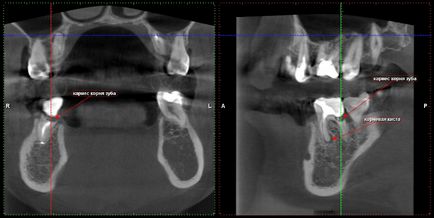

Minősége gyökértömés (töltési) csatornák és a jelenléte cisztás folyamatok körül tetejét a fogak

fogszuvasodás és a foggyökér

Ciszta maxillaris fog, fogeredetű arcüreggyulladás